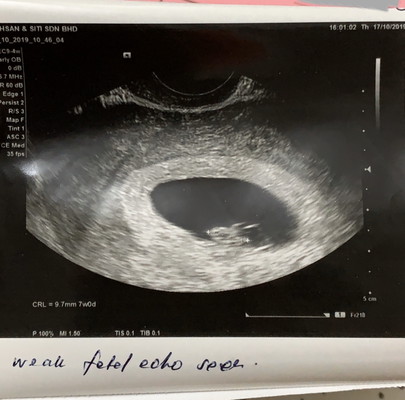

Assalamualaikum semua. Ada tak yg pernah jadi mcm saya? Mengandung selepas gugur, takdpt comfirm tarikh lagi. Semalam cek kk, doc kk kata kemungkinan janin sy da mati sbb tak membesar drpd mcm 2w ago. Tapi sy takde simptom2 gugur then doc ckp sy termasuk dalam kategori Missed Miscarriage ☹️ Petang tu, sy terus ke klinik swasta dan doc scan tvs. Alhamdulillah nampak baby, kantung okay tapi jantung lemah katanya. Dan ukuran usia baby baru 7w. Adakah normal utk 7w jantung tak berapa jelas @ bunyi dia tak kuat? Lepas dgr doctor kk ckp mcmtu semalam, saya agak sedih dan fikiran terganggu jugak la ? #KaliKeduaPregnant #FirstGugurWaktu5w